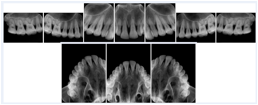

3. A dental provider wishes to capture a series of DICOM IO images for the patient’s dentition. The tooth morphology, teeth are divided into molars, premolars, canines and incisors, and a number of images for each jaw. The anatomic information was captured utilizing the triplet of schema. This standard code sequence is based on ISO 3950-2010, Dentistry - Designation system for teeth and areas of the oral cavity.

Every IO image should have anatomic information either through the primary or modifier sequence.

In most standard cases, images are oriented in structured layouts. These structured displays are useful to be shared between providers for reference purposes.

Table OO.1.1-1 shows structured display standard templates, where Viewset ID is based on the Japanese Society for Oral and Maxillofacial Radiology (JSOMR) classification provided by JIRA (Japan Medical Imaging and Radiological Systems Industries Association, www.jira-net.or.jp). Expected or typical teeth to be imaged location, region and designation codes are based on ISO 3950-2010, Dentistry - Designation system for teeth and areas of the oral cavity. For all the hanging protocols listed in OO.1.1-1, the value to use for Hanging Protocol Creator (0072,0008) is "JSOMR" and the value to use for Hanging Protocol Name (0072,0002) does not include "JSOMR" (e.g., "DL-S001A", not "JSOMR DL-S001A").